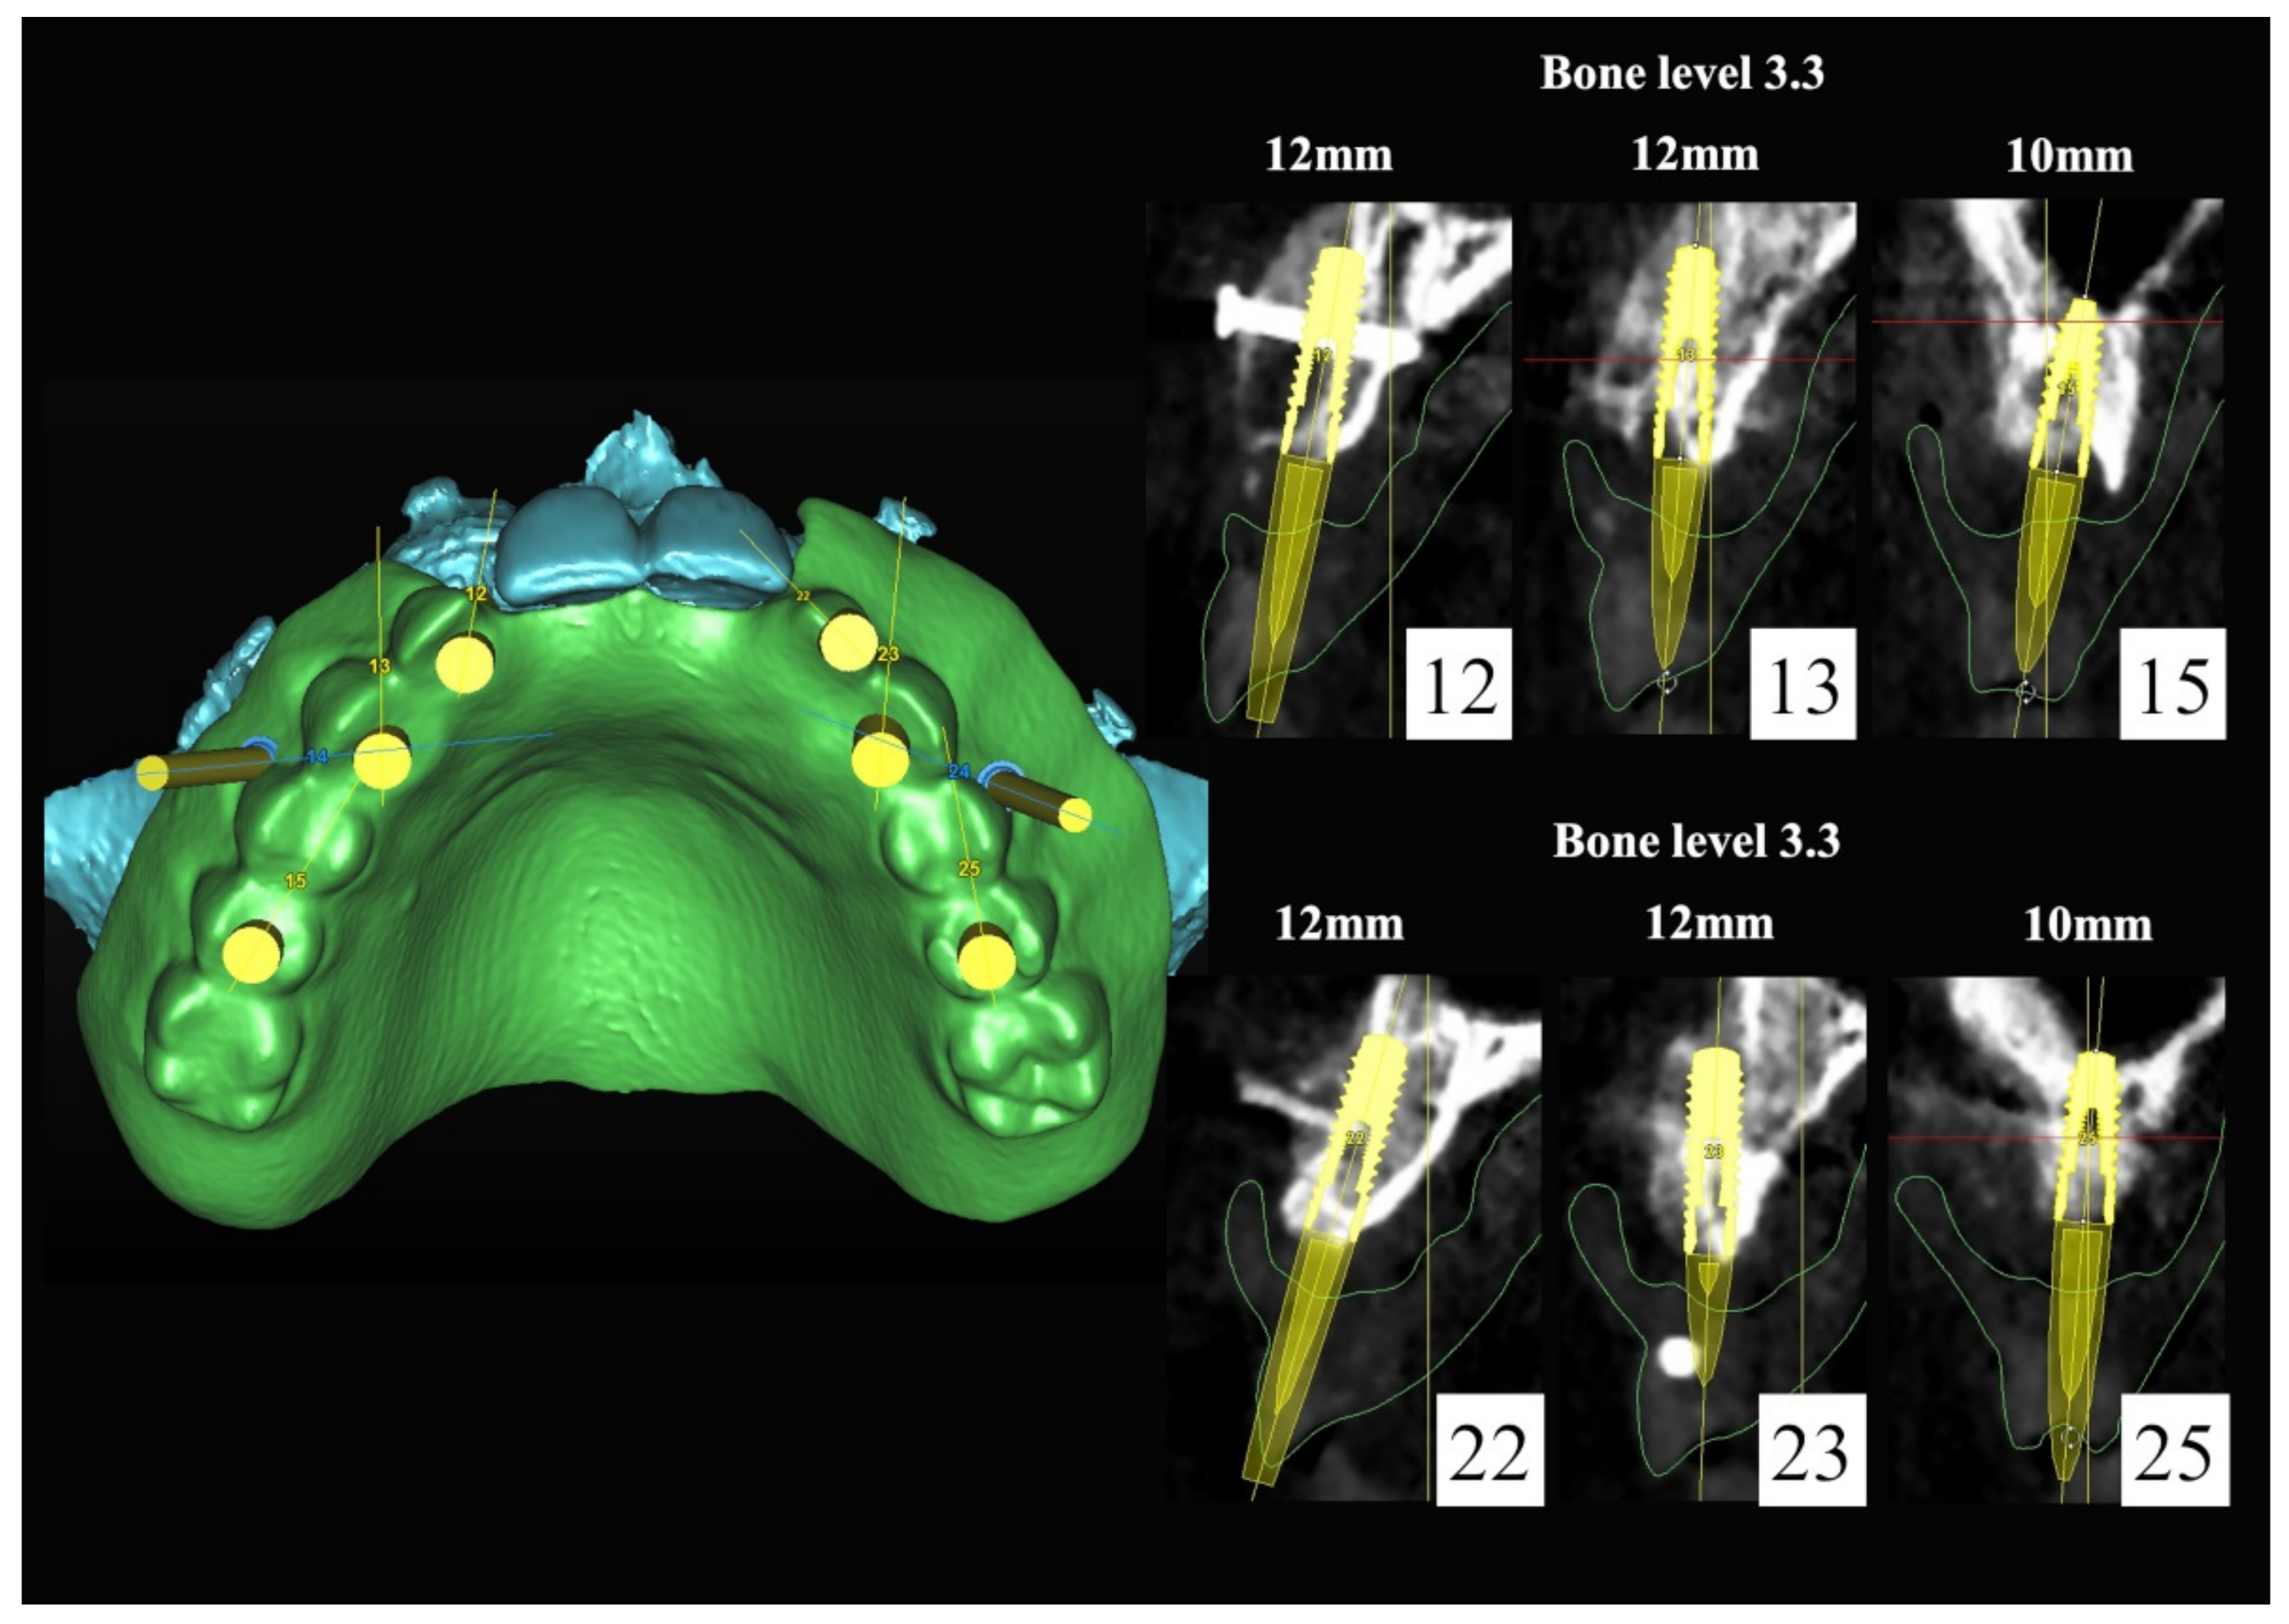

6.2.3. Image Segmentation and Virtual Planning:

The number, the length, the diameter and the placement of computational virtual implants were determined with respect to the design of the final prosthesis the available residual bone volume and the anatomical limitations according to the previously described technical procedure (Figure 16, Figure 17, Figure 18, Figure 19, Figure 20 and Figure 21).

Figure 18.

Three-dimensional (3D) planning of the number, the diameter and the axis of dental implants with respect to the design of the final virtual maxillary prosthesis.

Figure 19.

6.2.4. Intra-Operative Documentation:

In March 2013, twelve guided dental implants were placed at sites # 12, # 13, # 15, # 22, # 23, # 25, # 33, # 34, # 36, # 43, # 44, and # 46 (Figure 22, Figure 23, Figure 24, Figure 25 and Figure 26)